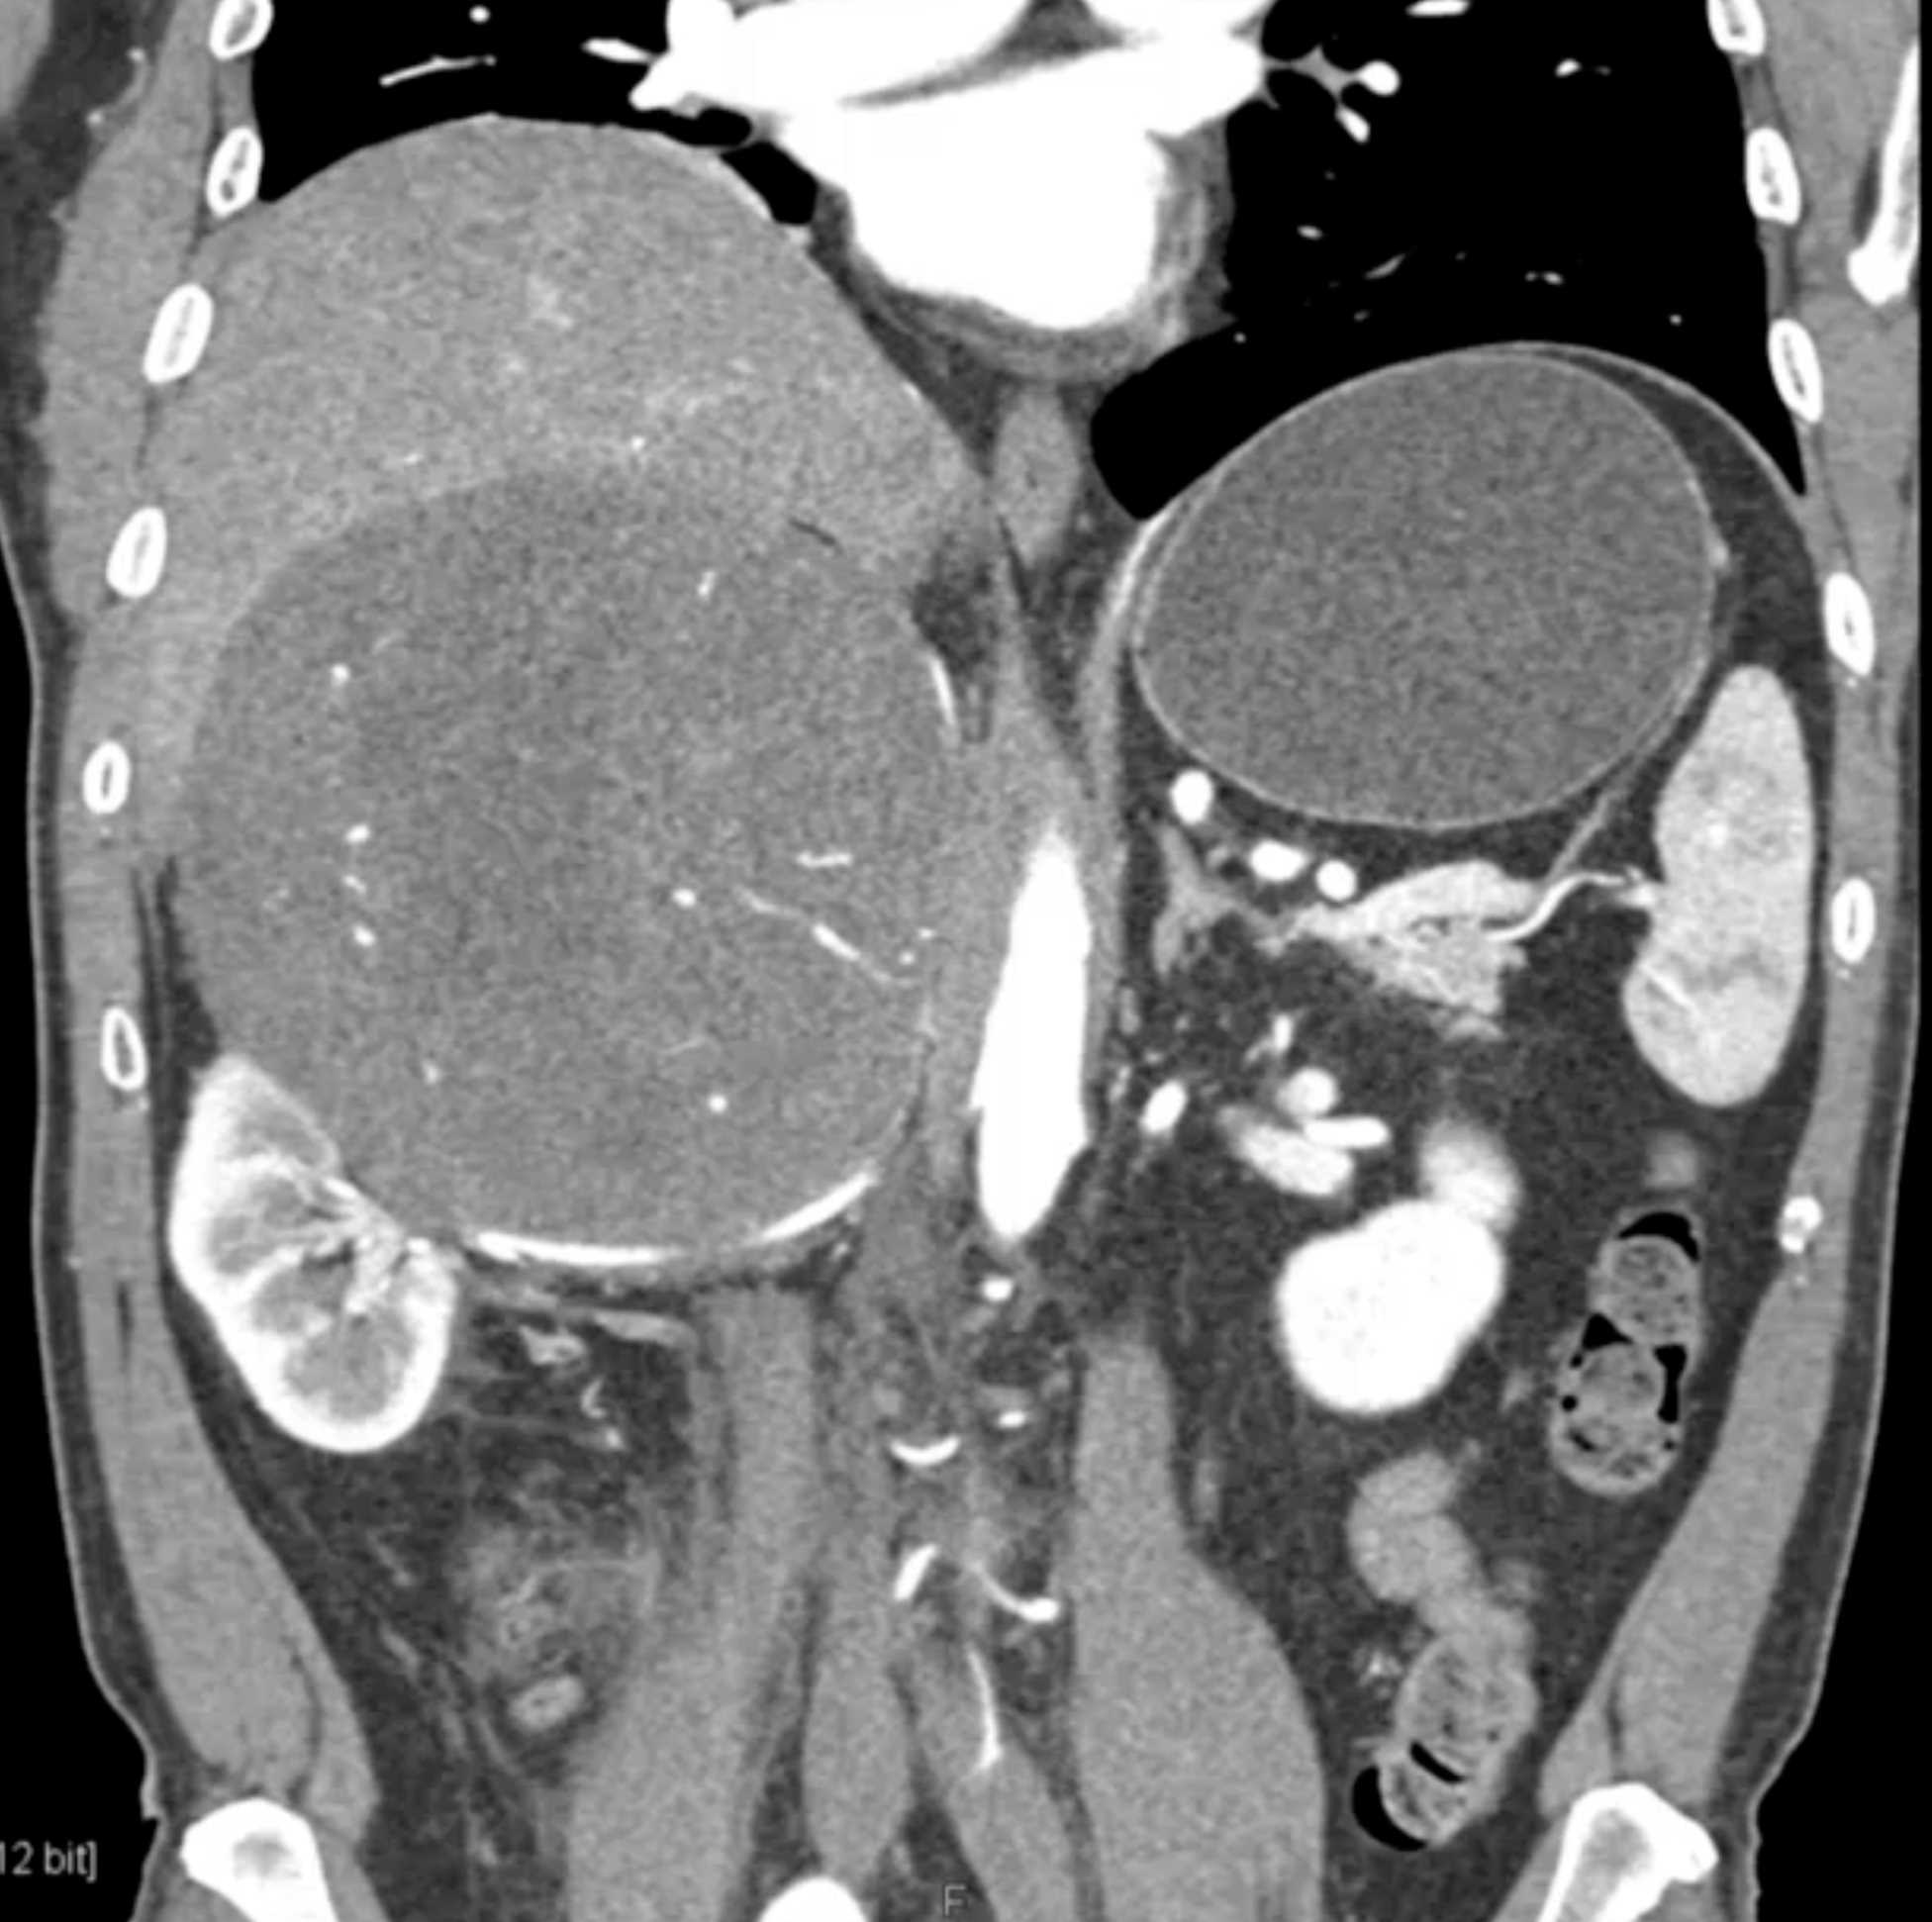

Left Adrenal Metastases from Renal Cell Carcinoma